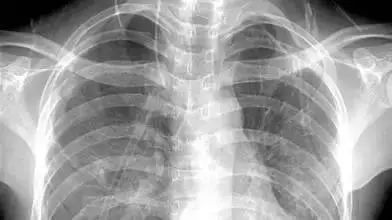

X光:像把面包压扁了看

X光会穿过人体,遇到被遮挡的部位,底片上不会曝光,洗片后这个部位就是白色的。

就像一片面包或一块棉花,看不到里面的纤维纹理,但用手压瘪了会清晰一些。X光最大缺点是受制于深浅组织的影像相互重叠和隐藏,有时需要多次多角度拍摄X光片。

X线摄影的原理是基于人体组织之间有密度和厚度的差别,当X线透过人体不同组织结构时,被吸收的程度不同,所以到达荧屏或胶片上的X线量即有差异,形成明暗或黑白对比不同的影像。

普通X线摄影因速度快,成本低廉,在临床中广泛应用,肿瘤诊疗中常用的X线主要包括胸腹部平片、骨关节摄影,以及胃肠道造影和乳腺普通X线摄影检查,其余检查方法因敏感性太低或无对应适应证,应用较少。

3、胸部——粗看X光片,细看CT

X光胸片可粗略检查心脏、主动脉、肺、胸膜、肋骨等,可以检查有无肺纹理增多、肺部钙化点、主动脉结钙化等。

胸部CT检查显示出的结构更清晰,对胸部病变检出敏感性和显示病变的准确性均优于常规X光胸片,特别是对于早期肺癌确诊有决定性意义。但是CT检查的辐射剂量高于X光。核磁对于肺部疾病的诊断,应用非常有限。